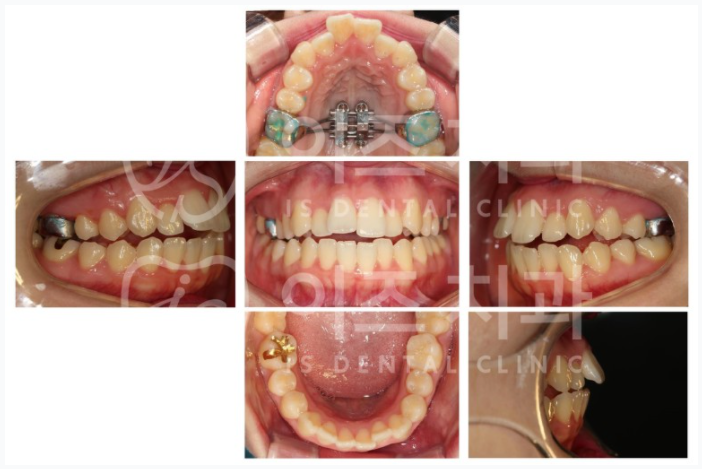

이런 방식으로 비발치로 끝낸 케이스를 하나 보여드리고 급마무리를 하려고 합니다 ^^

어떻게 보이시나요?

뭐 그렇게 삐뚤하지는 않은 거 같고, 가지런한 편이지요?

근데 이는 잘 안 맞는 것이 보이실까 모르겠습니다. 교합이 잘 안 맞는다고 표현하지요.

더 심한 환자도 많지만 느낌을 좀 더 잘 알 수 있어서 이 케이스를 골랐는데요.

이 정도만 되도 상악을 확장하는 것이 좋겠습니다.

이 상태로 치아만 배열하게 되면 정확한 교합을 맞추기가 어려워집니다.

장치를 장착한 사진입니다.

이 단계에서는 보통 치아에 붙이는 브라켓은 아직 하지 않습니다.